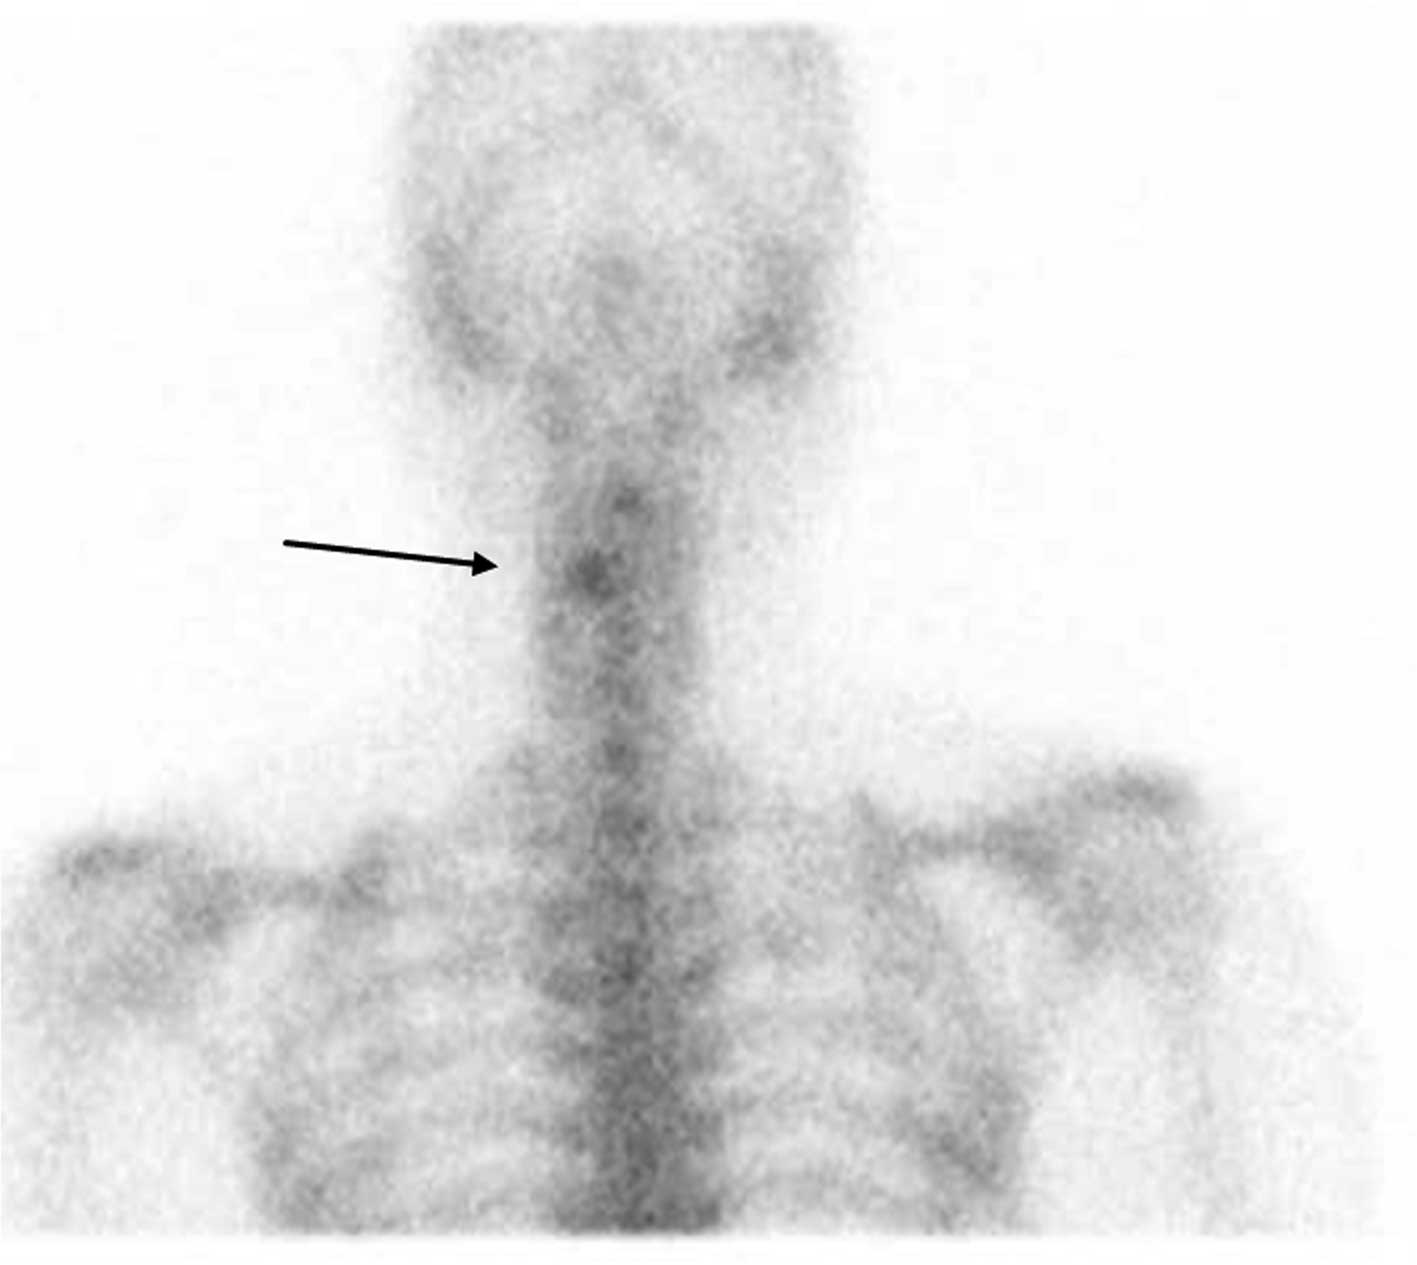

Остеома ребра: примеры рентгенограмм и диагностические признаки